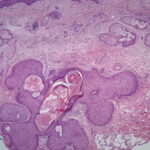

Middle-aged and elderly individuals are commonly

affected. Pilar sheath acanthoma is characterized by a small (5 to 10 mm in diameter), solitary, skin-colored papule situated on the head and neck, particularly around the upper lip. A central, occasionally keratin plugged pore is often present. Histologically, there is a crateriform depression in the epidermis representing a widely dilated, keratin-filled infundibulum or closely set infundibula contiguous at the base with numerous epithelial lobules of pink keratinocytes. The epithelial lobules radiate into the dermis, sometimes with involvement of the subcutis. They are surrounded by a narrow rim of fibrous tissue. The epithelium shows similar features to those of the isthmus of a normal hair follicle. Small infundibulocystic structures, tubular structures, and foci of sebaceous differentiation (ducts or sebaceous lobules) are variably observed in individual cases. Treatment is surgical excision